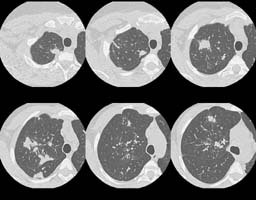

HRCT images:

(Click small pictures to view larger radiographs)